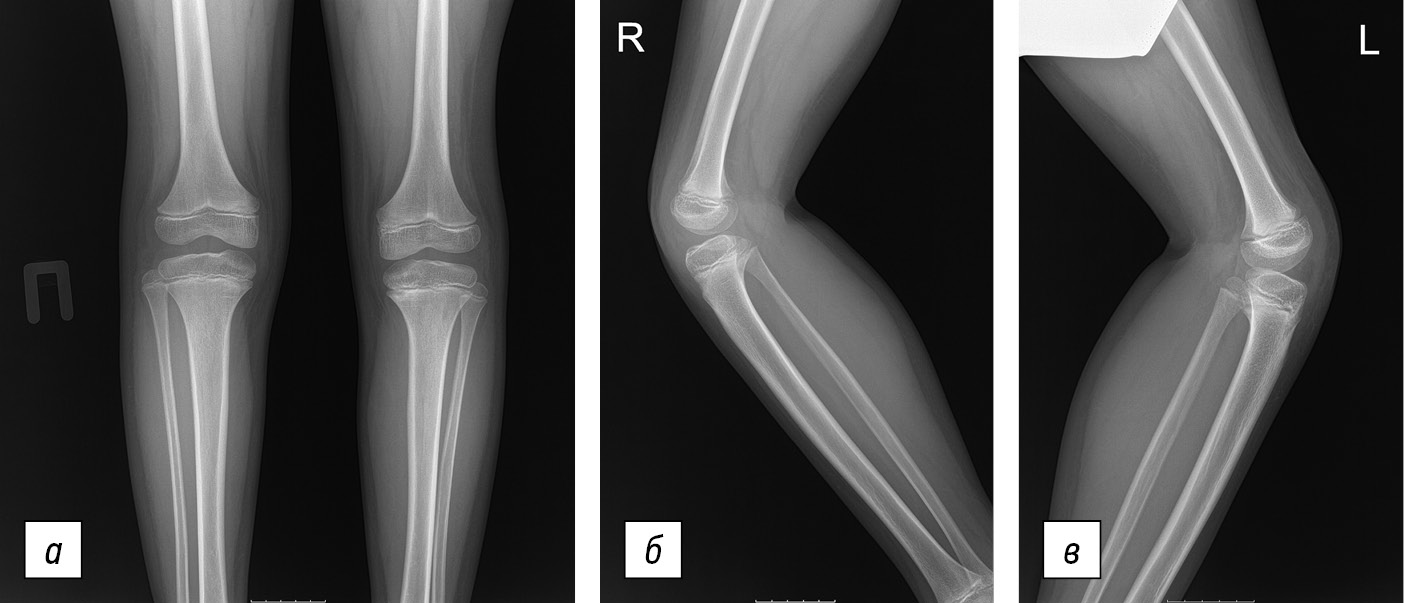

Fig. 5. X-ray of patient P., age 10 years, after treatment: a — direct projection; b — lateral projection of the right knee joint (patellar aplasia); c — lateral projection of the left knee joint (patellar aplasia)